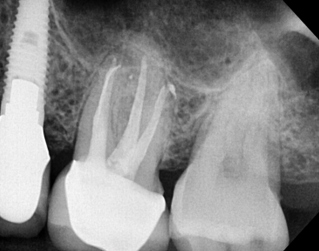

CBCT Scans provide a 3D dental image, while traditional X-rays are only a 2-dimensional picture of the mouth. This means that with traditional X-rays alone, it is very difficult to diagnose non-painful lesions like dental abscesses that are within the jaw bone.

Here are some examples of photos of bone lesions

Patient “A ”Xray of a root canal tooth #14 CBCT Scan of same tooth #14, notice the lesion on the bone at the tip of the left root Notice root canal #13 on xrays CBCT Scan on same tooth #13, there is a lesion at the tip of the root causing sinus membrane inflammation. Patient “C” xray tooth #14 Patient “C” CBCT Scan tooth #14, bone lesion affects both roots. Upland Lighthouse Dentistry, a renowned family dentist in Upland, offers cone beam CBCT scan technology for comprehensive dental care. Our expert dentist utilize this advanced 3D imaging technique to obtain precise details of dental structures, soft tissues, and nerve paths, enhancing our diagnostic accuracy and treatment planning. Contact Upland Lighthouse Dentistry today!